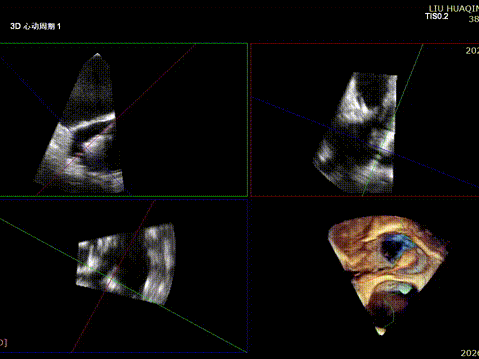

The operation was performed in a hybrid operating room and completed under the guidance of real-time three-dimensional transesophageal echocardiography (3D TEE) and X-ray fluoroscopy throughout the entire process.

Tricuspid Valve Annuloplasty Stage:Subsequently, via the right internal jugular vein approach, the K-clip® transcatheter tricuspid valve annuloplasty system was delivered to the right atrium. With the assistance of three-dimensional ultrasound stereoscopic views, a 12T clip was successfully implanted at the posteroseptal commissural annulus of the tricuspid valve, and a 14T clip at the anteroposterior commissural annulus, achieving effective constriction of the dilated annulus. Immediate postoperative assessment demonstrated that tricuspid regurgitation was improved from severe (4+) to mild (1+) instantaneously.

1.Intraoperative baseline assessment of regurgitation severity

2.Placement of large sheath and delivery system under ultrasound guidance

3.Steer and rotate the delivery system to target the lesion, and implant the anchor screw via the 3D MPR plane

4.Land the clamping arms after orientation adjustment, and close the clamping arms slowly

5.Perform the same procedure for the second clip; the clip morphology is stable under 3D imaging